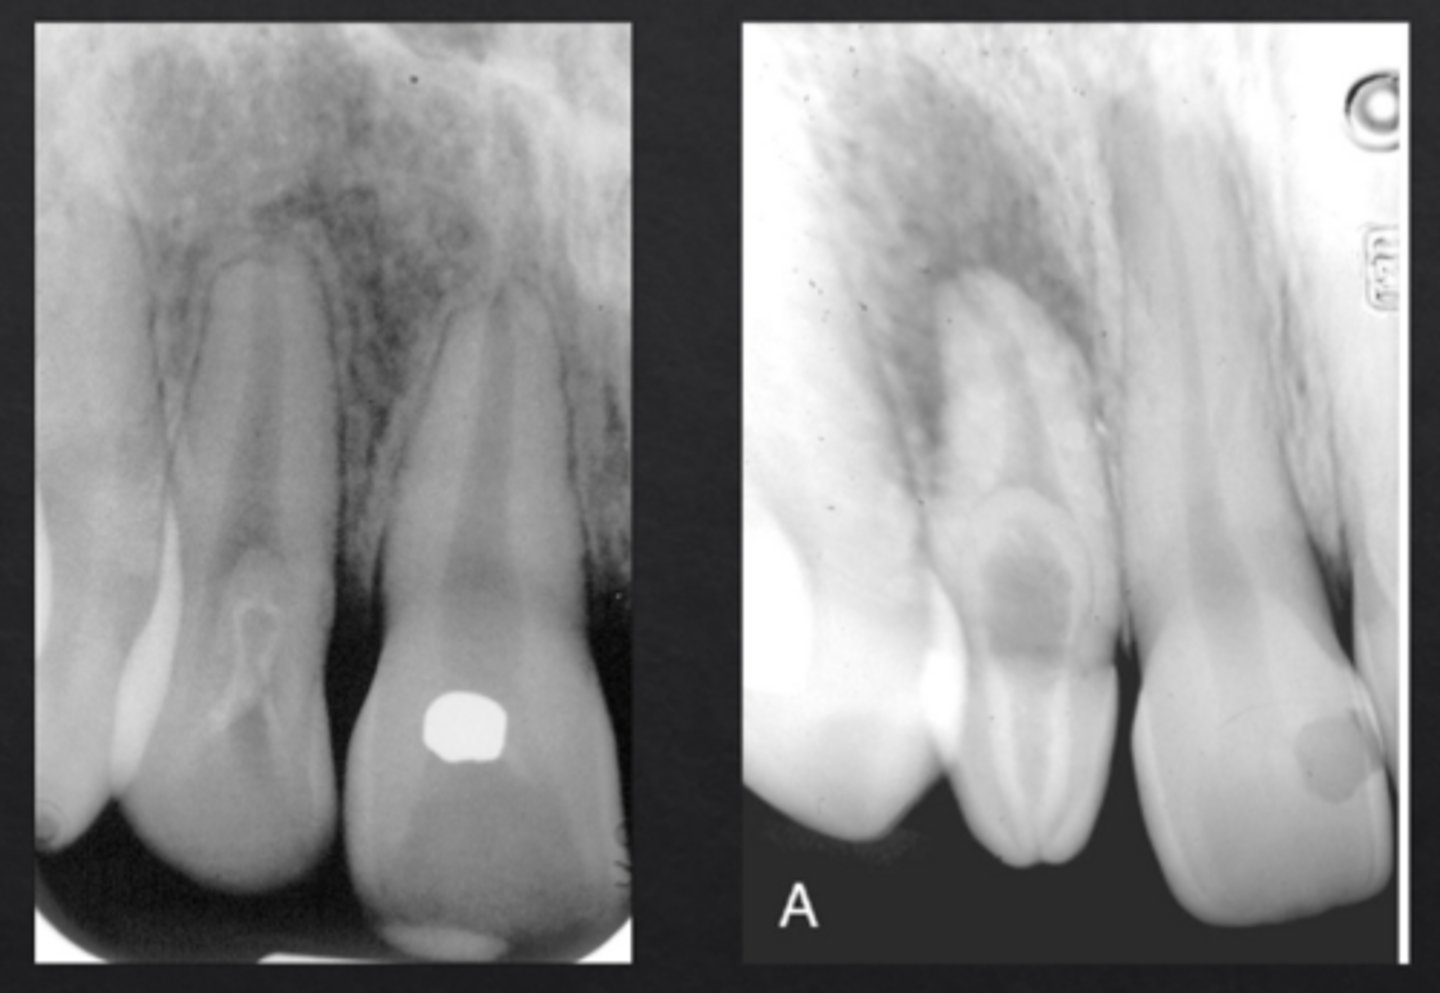

What is dens invaginatus (dens in dente)?

Infolding of enamel into the tooth, forming "tooth within a tooth"

Which tooth is most commonly affected by dens invaginatus?

Maxillary lateral incisors

What is a mesiodens?

Supernumerary tooth between maxillary central incisors

What is an enamel pearl?

Small globule of enamel on the root surface or CEJ

Where are enamel pearls most often found?

Furcation of molars

Why are enamel pearls clinically important?

they prevent normal periodontal attachment and may cause perio bone loss